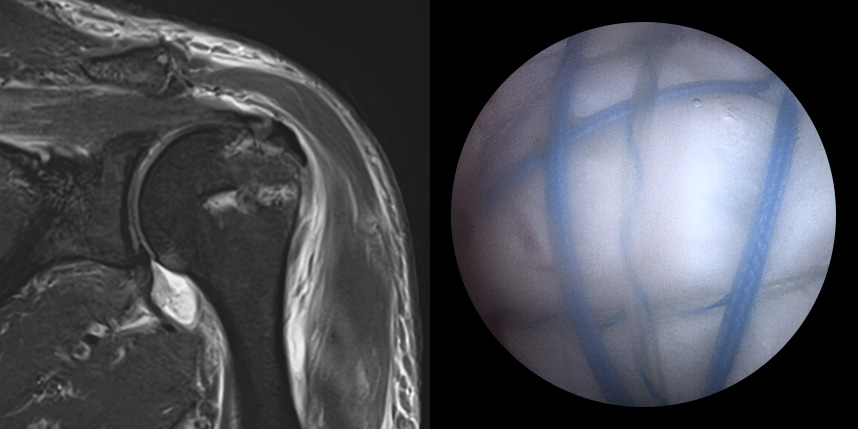

MRI상 회전근개 파열이

진행되는 경우

일열 봉합술

브릿지 봉합술

접촉면접과 힘줄

부착 압력이 높습니다.

초기,중기,말기 파열에

주로 사용됩니다.

상대적으로

재파열율이 낮습니다.